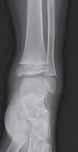

Podział złamań kości rosnących, tzw. złamań nasadowych: A – schematyczne przedstawienie klasyfikacji złamań; B – SH I (RTG, widok z przodu i z boku); C – SH II (RTG, widok z przodu i z boku); D – SH II (TK, widok z boku); E – SH III (RTG, widok z przodu i z boku); F – SH IV (RTG, widok z przodu i z boku); G – SH V (RTG, widok z przodu i z boku).

Rozpoznanie

Objawy złamania to silny ból uniemożliwiający stanie i chodzenie, zniekształcenie obrysów stawu kolanowego przez krwiak i różnego stopnia przemieszczenie nasady kości piszczelowej. Należy dokładnie zbadać stan ukrwienia i unaczynienia kończyny pod kątem objawów uszkodzenia tętnicy podkolanowej i nerwu strzałkowego. Trzeba ocenić bolesność uciskową oraz napięcie w przedziałach powięziowych podudzia: przednim, bocznym, tylnym powierzchownym i tylnym głębokim. U pacjentów z podejrzeniem wzmożonego ciśnienia wewnątrzprzedziałowego należy wielokrotnie powtarzać badanie ukrwienia i unerwienia kończyny, a w razie zaistnienia wskazań wykonać bezpośredni pomiar ciśnienia w przedziałach. Powinno się zawsze podejrzewać możliwość uszkodzeń więzadłowych współistniejących ze złamaniem. Badania obrazowe to RTG w pozycji AP, bocznej i skośnej. Wykonanie badania TK może być konieczne w celu pełnej oceny rozległości

złamania. W przypadku podejrzenia uszkodzenia tętnicy podkolanowej należy wykonać angio-TK lub arteriografię.